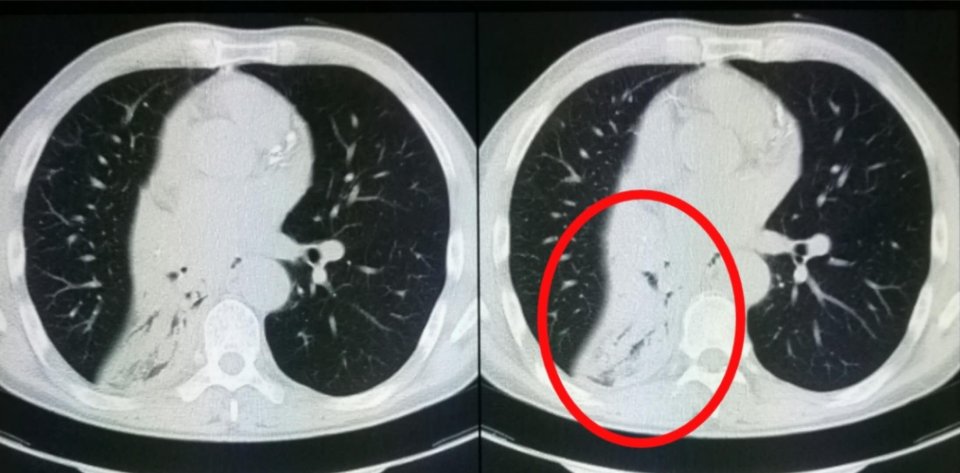

3.老年男性,吸烟多年,咳嗽,经支气管镜病理确诊的右下肺小细胞肺癌患者,合并右下叶肺不张:

没有手术条件,经综合治疗(放化疗为主)四年后,没有复发:

对小细胞来讲,这种治疗效果显著、并获得长期生存的比较少见。

但少见不代表没有!活着就有希望!

小细胞肺癌现在仍然是放化疗为主的综合治疗,没有靶向药物,但很多医学家们正在尝试寻找适合的靶点,期待他们的成功!